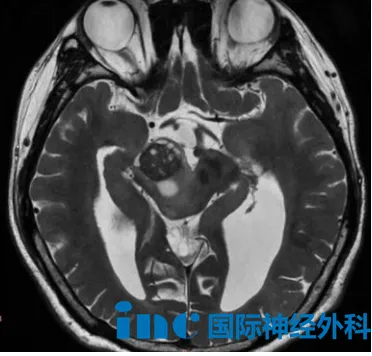

9个月男宝脑干胶质瘤

9个月的男宝小星星,出生3天即因脑积水接受了脑室-腹腔分流术。8个月大时,他出现双侧眼睑下垂和斜视症状,经检查发现中脑、四叠体、丘脑区域存在异常信号,临床初步怀疑为胶质瘤,多数医生建议继续观察。

巴教授特别强调,这可能是一个位于中脑的弥漫性胶质瘤,单靠手术是无法解决肿瘤问题的。谨慎地选择手术治疗,这样不仅可以缩小肿瘤的体积,更重要的是,能够获得明确的组织病理学和分子生物学诊断结果,这些诊断结果将是选择最佳辅助治疗方案的重要依据。对婴幼儿而言,盲目化疗或放疗风险极高。